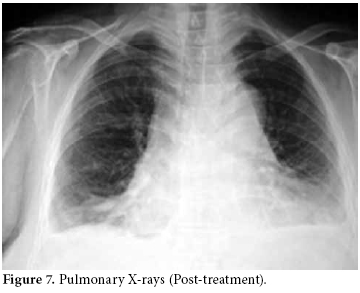

Pulmonary X-rays showed moderate and severe bilateral pleural effusion, more pronounced in the right lung, and an increased cardiothoracic index.

The pericardiocentesis fluid and blood cultures were negative, and the control ECHO was normal in the third and fifth days. The effusion had completely disappeared. Therefore, taking into account all clinical, radiological, and laboratory findings, the patient was diagnosed with DILE due to the use of sulphasalazine. Existing minimal pleural effusion was reported by the pulmonary disease department (figure 7). Liver enzyme and ferritin levels were normal. The other laboratory changes before discharge were as follows: leukocyte count: 18800/mL, Hgb: 12.7 g/dl, CRP: 3.84 mg/L, RF: 37 IU/mL (0-15), ESR: 22 mm/hour, anti-CCP: positive, ANA: negative, anti-histone antibodies: positive, and anti-dsDNA: negative. Urine analysis findings were within normal limits, and the DAS was calculated as 3.06.